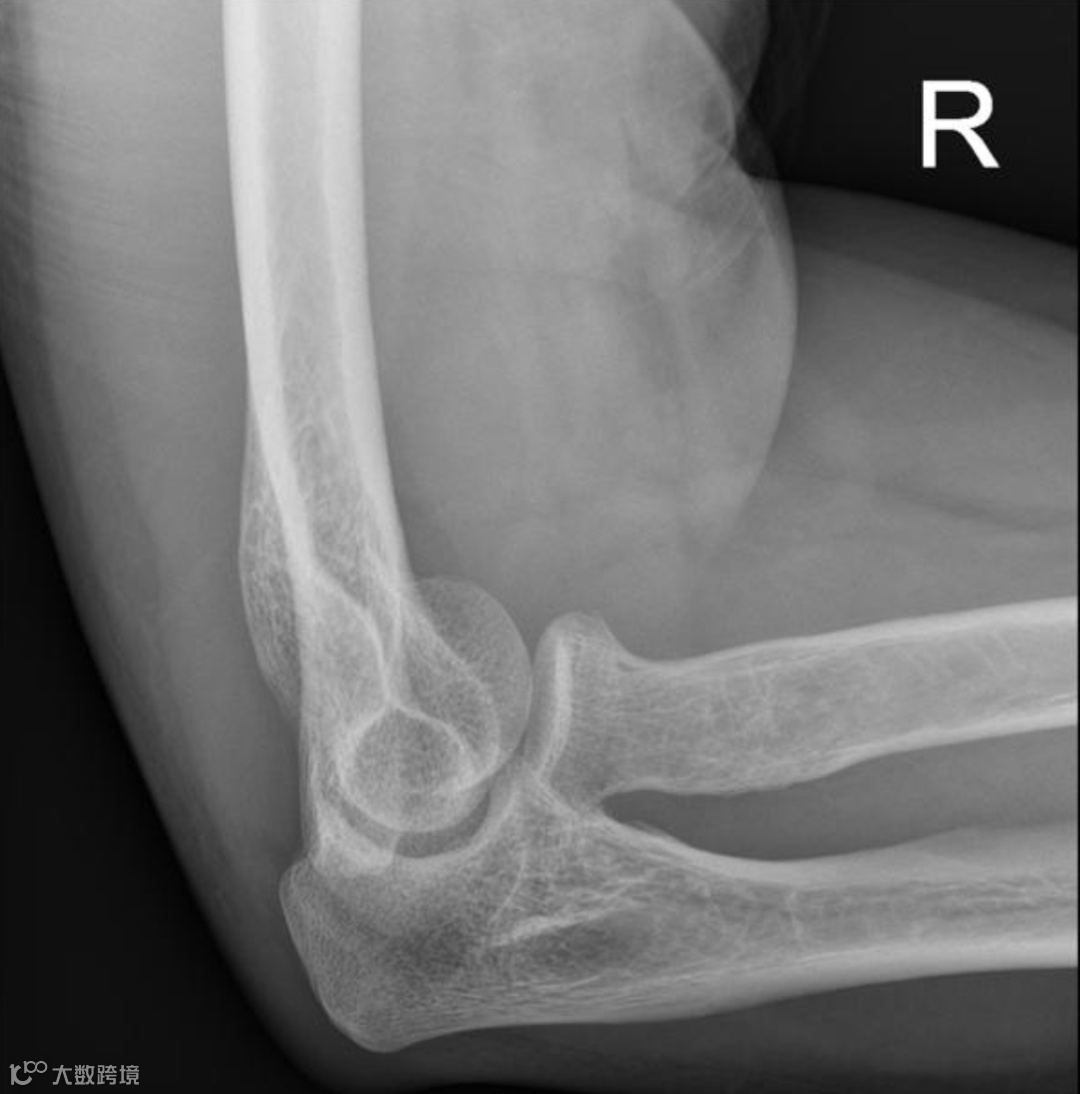

男,35岁,右肘部外伤。未见明确骨折,X线显示前脂肪垫征 [由于关节积液(黄色)将正常的肱骨前脂肪垫向上抬离其正常位置,在侧位投影上呈现三角形(蓝色)]。 关节积液较多提示可能存在骨折,最有可能的是桡骨头骨折。建议7至10天后复查X光片。

同一患者,10天后复查右肘关节,X线斜位显示持续存在的帆征(蓝色)。桡骨头前侧皮质骨缺损可见,证实关节内骨折存在,但未移位且隐匿。